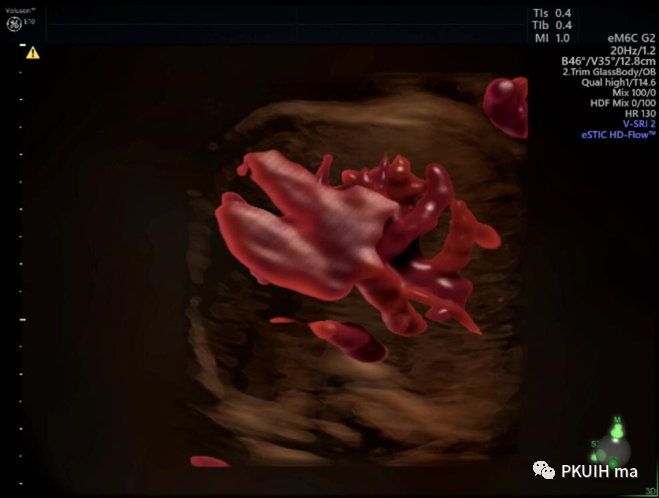

四维血流现象呈现脐带打结

四维血流显示脐带插入点和胎盘绒毛血管